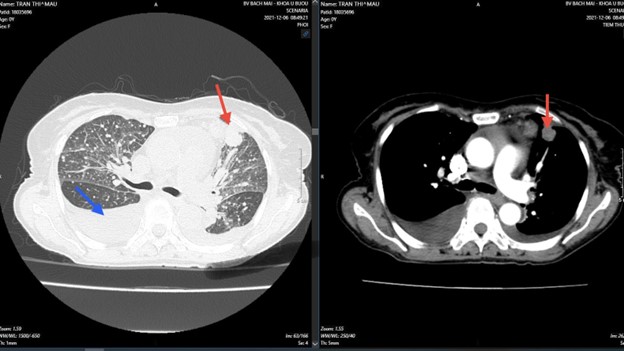

+ Sau điều trị 3 tháng:

Hình 2: Kích thước khối u sau điều trị đã giảm và nhỏ lại nhiều, giảm rõ rệt tràn dịch màng phổi so với trước điều trị